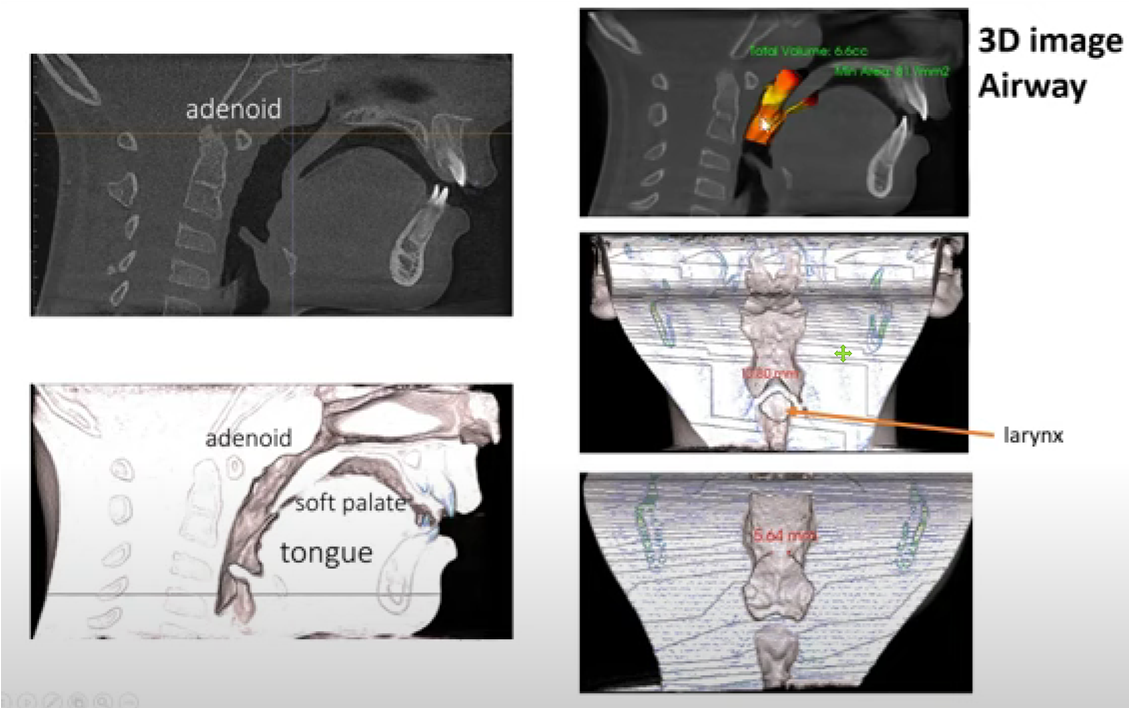

According to statistics, OSA is very prevalent, affecting about 34% of men and 17% of women aged 30-70 years. Due to the inconvenience of the use of positive pressure respirators, the effectiveness and convenience of oral devices can popularize the treatment of OSA. As a result, the C4 airway correction system has a large market to be developed. According to the "Overview of China's Oral Medical Service Market", in 2019, there were 885 dental specialties and about 7,000 dental departments in China(Including 6,287 secondary and tertiary general hospitals, 74 tertiary integrated traditional Chinese and Western medicine hospitals, 450 beauty hospitals, and 141 children's hospitals); National Medical Institution Inquiry System of the National Health Commission, As of December 24, 2020, there are 71,397 oral (dental) clinics nationwide. These hospitals or clinics will be the base for the promotion of the C4 airway correction system.

The market positioning of respiratory orthodontic systems is mainly aimed at those patients with snoring and obstructive sleep apnea (OSA), This is especially true in people who have difficulty or are unable to use positive pressure respirators. The advent of such devices offers an alternative that is more suitable for them, aimed at improving their breathing problems and sleep quality.

According to market analysis, the prevalence of obstructive sleep apnea (OSA) is quite high. Studies have shown that the condition affects about 34% of middle-aged and older men and 17% of middle-aged and older women. As a result, there is a large potential consumer base in this market.

On the other hand, dentists are important partners in the respiratory orthodontic system due to their advantages in the diagnosis and treatment of obstructive sleep apnea, as well as their use of specialized equipment such as cone beam computed tomography (CBCT).

In China, the size of the oral medical services market is quite large. According to statistics, in 2019, there were 885 dental hospitals and about 7,000 dental departments in hospitals, and by December 24, 2020, there were 71,397 oral (dental) clinics/outpatient departments nationwide. These establishments could serve as a base for the promotion and sale of the SNOSA respiratory system.

In addition, the system's custom design, including C4 braces, palate slow bone expansion and Angel therapy, allows it to more precisely meet the needs of patients and provide more effective and comfortable treatment options, which is also a major advantage in the market.

According to some reports, snoring and sleep apnea syndrome (OSA) are common problems for a large portion of the population, and these problems are likely to worsen as obesity rates increase. Snoring and sleep apnea are not just sleep problems, they are also linked to health problems such as heart disease, stroke, diabetes, and more. However, most of those affected are not diagnosed or treated.